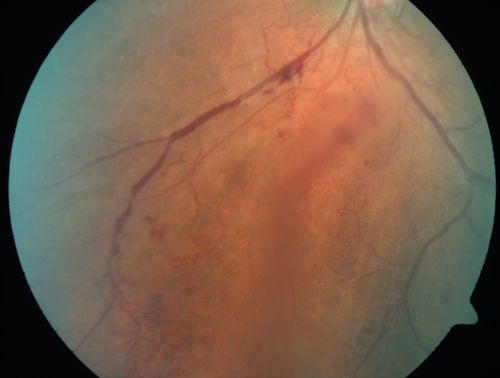

Proliferative Diabetic Retinopathy - Moderate - mild NVD with NVE

Venous beading, vascular loops and NVE are visible on photos